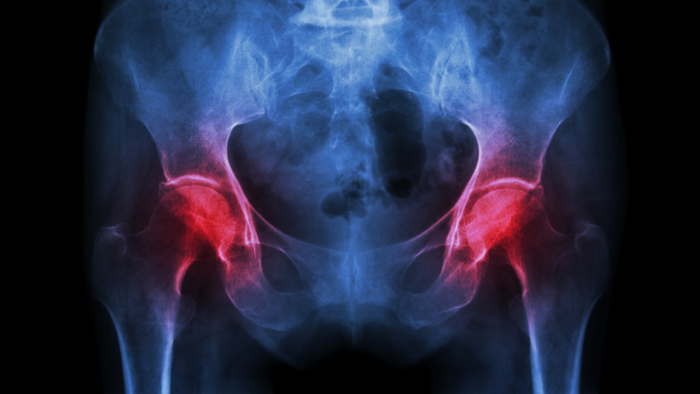

hip joint x-ray showing osteoarthritis

When everything’s working as it should, your joints allow you to move through life with ease, whether you're going for a walk, dancing in your kitchen, or playing with your grandkids. But when arthritis strikes, it’s like throwing a wrench into a finely balanced system.

• Cartilage breaks down

• Inflammation invades the synovial lining

• Subchondral bone stiffens

• Supporting muscles and ligaments weaken

Understanding what’s going wrong at this structural level helps us not only grasp why arthritis hurts but also guides us in finding better ways to manage it, from medications and exercise to joint replacement or regenerative therapies. In the next few sections, we’ll home in on exactly how arthritis develops and progresses, what’s happening at the cellular and chemical level, and why catching it early (or even better, preventing it) can be life-changing.